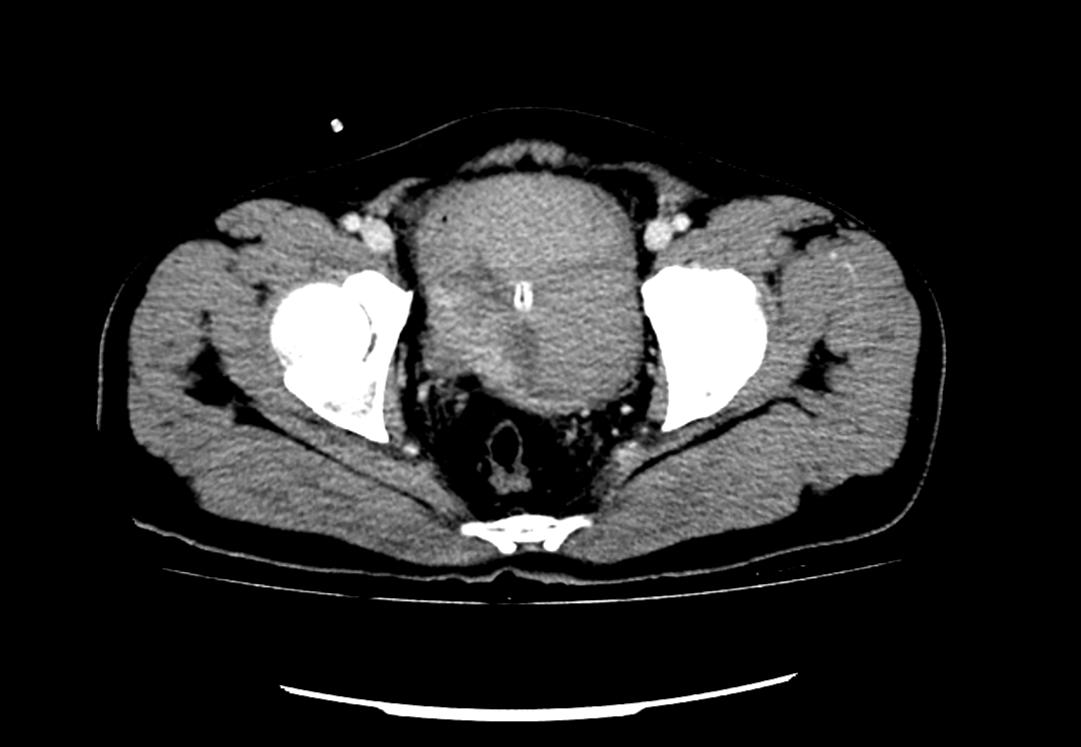

患者為53歲的男性,患者因肉眼血尿就診我院門診,行泌尿系CT考慮膀胱占位,建議患者住院治療,入院后完善膀胱MRI檢查進一步診斷膀胱腫瘤,侵犯肌層。行膀胱腫物激光切除后,病理學檢查明確“膀胱高級別尿路上皮癌,肌層浸潤”診斷,結(jié)合泌尿外科診療指南建議行根治性膀胱全切術(shù)。

泌尿外科醫(yī)生團隊術(shù)前將患者情況上報醫(yī)務科,并組織了多次會診。患者“肌層浸潤性膀胱癌”診斷明確,術(shù)前完善心肺功能排除無明顯手術(shù)禁忌,結(jié)合指南推薦及泌尿外科團隊成員綜合意見,決定在全麻下行腹腔鏡下膀胱根治性切除+盆腔淋巴節(jié)清掃+回腸代膀胱手術(shù)。術(shù)前嚴格完善準備工作,手術(shù)歷經(jīng)7小時,完整切除了患者的膀胱、前列腺及精囊,并行回腸代膀胱。手術(shù)順利,術(shù)后3天可正常行走,復查患者各項指標正常。